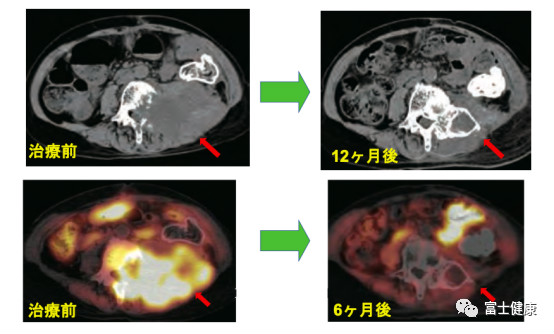

圖6.直腸癌術(shù)后再發(fā)例(69歲女性)

⑤直腸癌的手術(shù)后骨盆內(nèi)復(fù)發(fā)也是重離子治療適應(yīng)癥,局部控制率為90%以上,五年生存率50%,取得了非常好的治療成績。今后,遠(yuǎn)距離轉(zhuǎn)移的重離子治療是我們接下來的研究方向。